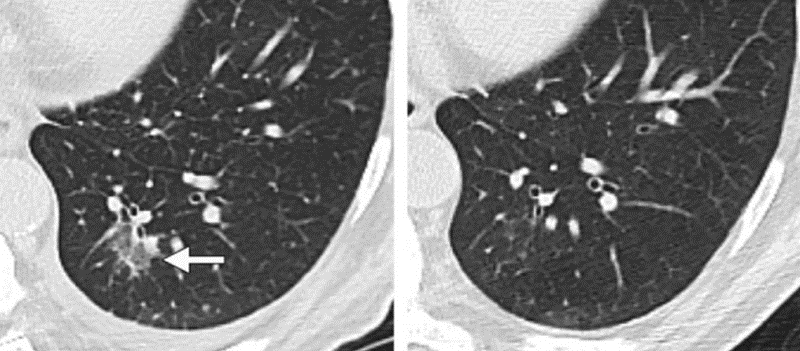

图1a                                           图1b

左下肺磨玻璃密度结节(图1a),患者有发烧病史,3个月后复查,病灶基本消失(图1b)。